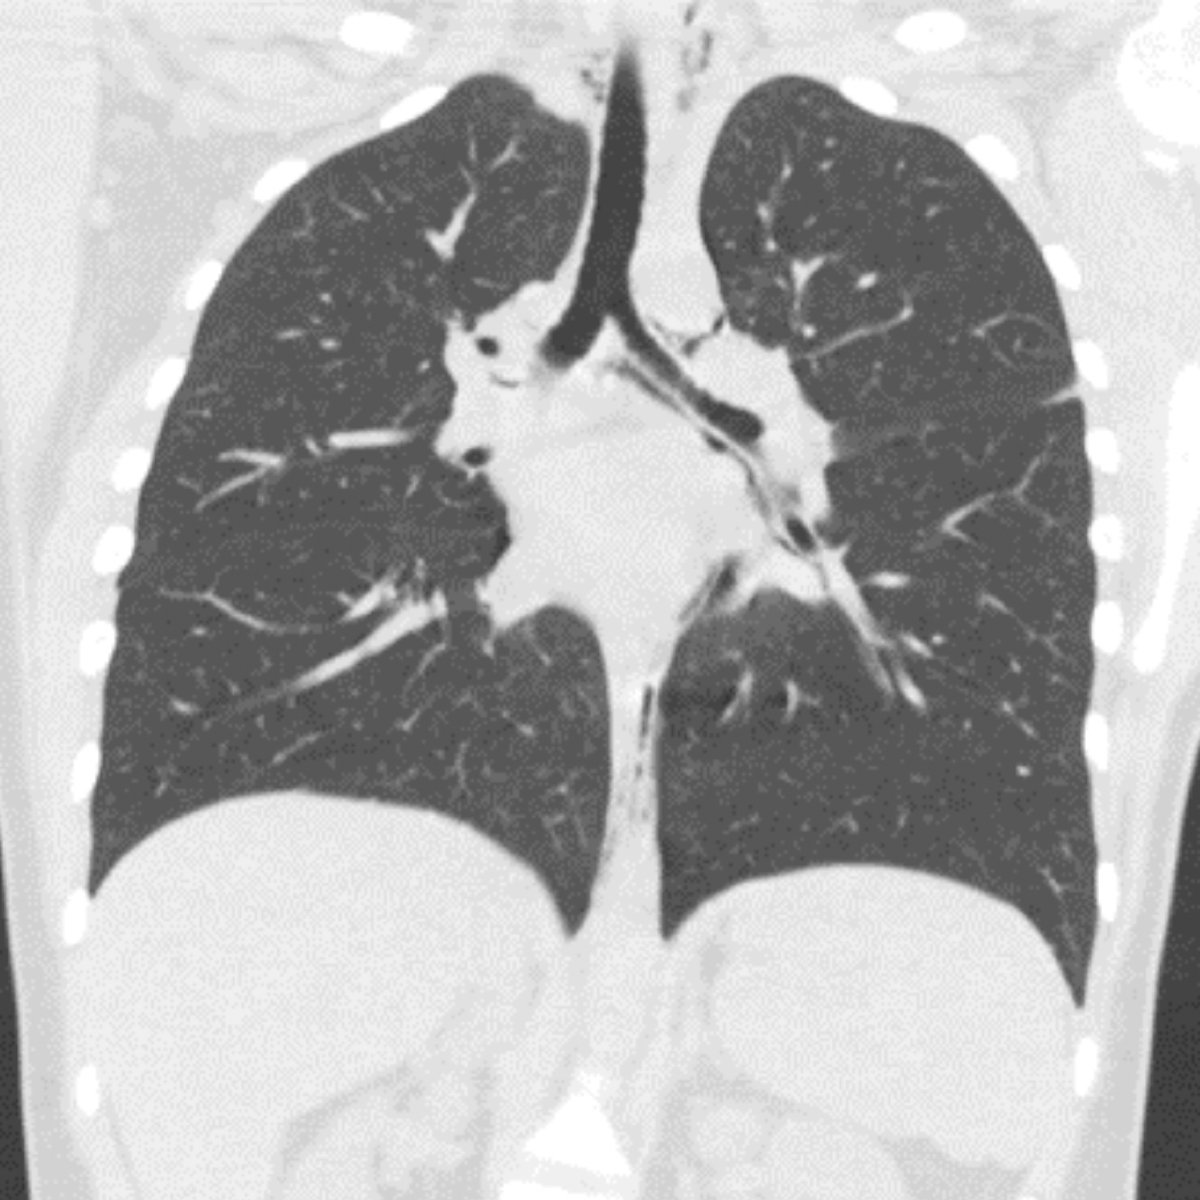

Have you seen our November 2022 Thoracic Case of the Month? 77 yo F w/ 40-year smoking history, presents with worsening shortness of breath and left rib pain… submitted by @AWSongMD & Joseph Lowry MD from Staten Island University Hospital. thoracicrad.org/assets/index/2…